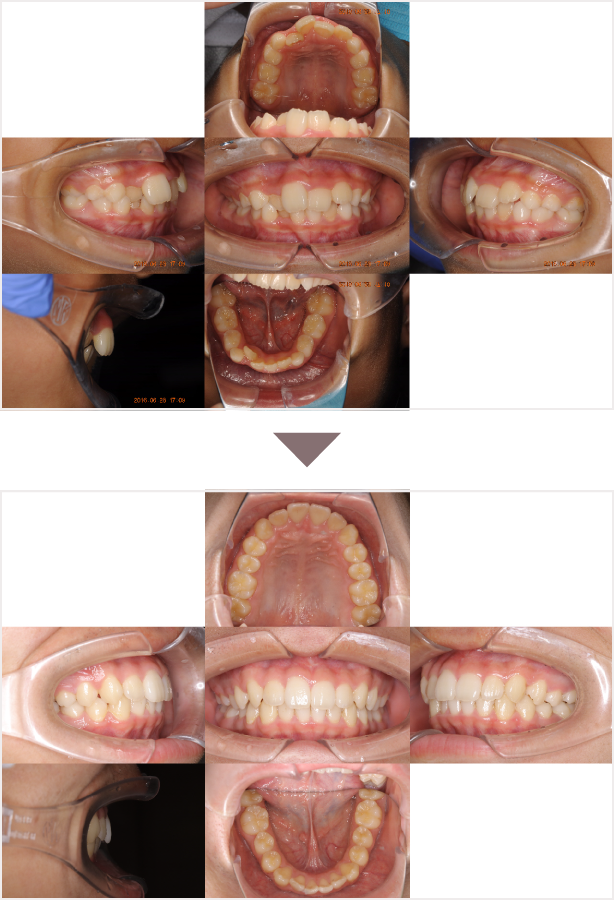

症例叢生

性別

期間8年8ヶ月

治療内容N-Bimler装置、Neo-Capを使用して治療

治療における

副作用・リスク

装着しないと効果は出ません

金額ビムラー装置:550,000円

ネオキャップ:4本

合計:572,000円